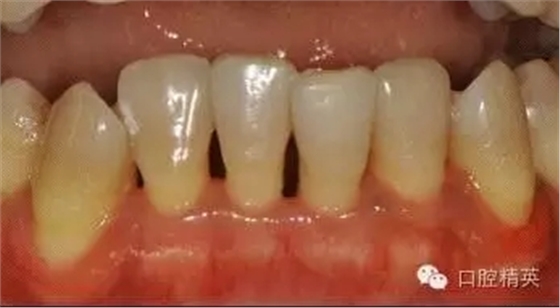

本病例 :女 34歲,主訴刷牙出血,覺牙齒輕度松動一年。

檢查見大量齦上及齦下結(jié)石,探診出血,牙周袋較深,32-42 II度松動。X線片顯示牙槽骨水平吸收。

診斷:成人慢性廣泛性中度牙周炎。

治療前: